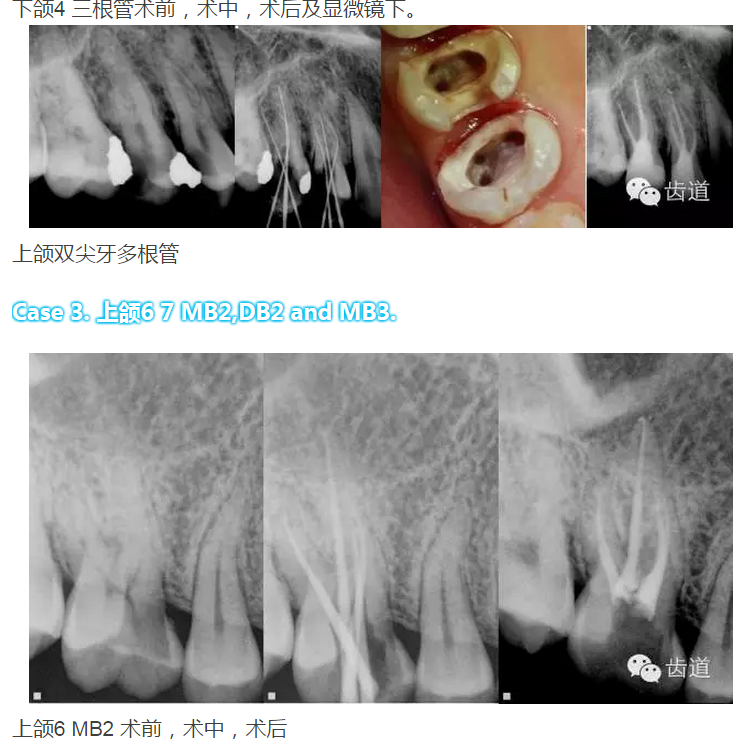

下頜第一磨牙:為3-4個(gè)根管,遠(yuǎn)中雙根管的發(fā)生率為51.4% 左右,側(cè)支根管發(fā)生率為30%左右;